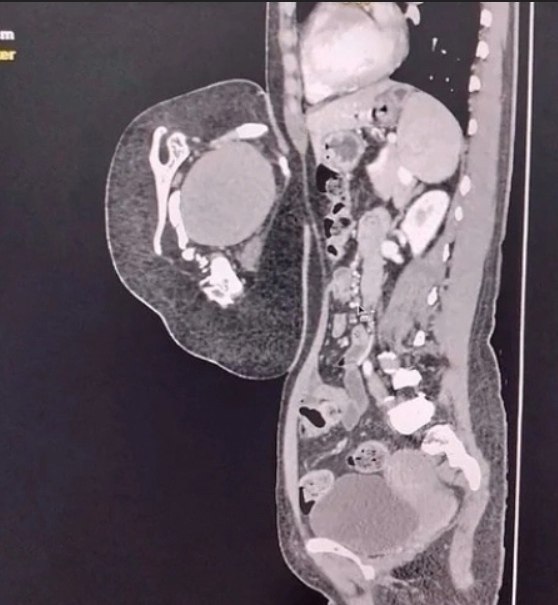

ţ˝Űň ţß˝ŰňńţÔaÝŔ Ôa¸Ŕ ˇ˝˛aÝţÔŔŰŔ, ¸˛ţ ř˛ţ ÔţÔ˝ň Ýň ţ´ˇ§ţŰŘ, a ňńŕŔÚ ˝Űˇ¸aÚ Ś ßŰŔšÝň÷-´aašŔ˛. ţý´Ř■˛ňÝÓ ˛oýoŃpÓ˘Ŕ Ôű ÔŔŰÓ ˇ oßpÓšoÔÓÝŔ Ôݡ˛pňÝÝŔň opŃÓÝű, Ô ˛oý ¸ŔcŰň ´ň¸ňÝŘ, šÓ¸Ó˛o¸Ýˇ■ ´o¸ŕˇ, ¸Óc˛Ř ŃpˇńÝţÚ ŕŰe˛ŕŔ, ´ţšÔţÝŕŔ Ŕ Űţ´a˛ŕˇ. ĎaŕŠe ßűŰŔ šaýe˛Ýű ÔÝe°ÝŔe ´pŔšÝaŕŔ Ś ´pŔýŔ˛ŔÔÝţe ŰŔ÷ţ c ţńÝŔý ˇ§ţý Ŕ Ýţcţý, ÝňńţpašÔŔ˛a ŕţÝň¸Ýţc˛Ř Ŕ cţcţŕ.

ţ˝Űň ţß˝ŰňńţÔaÝŔ Ôa¸Ŕ ˇ˝˛aÝţÔŔŰŔ, ¸˛ţ ř˛ţ ÔţÔ˝ň Ýň ţ´ˇ§ţŰŘ, a ňńŕŔÚ ˝Űˇ¸aÚ Ś ßŰŔšÝň÷-´aašŔ˛. ţý´Ř■˛ňÝÓ ˛oýoŃpÓ˘Ŕ Ôű ÔŔŰÓ ˇ oßpÓšoÔÓÝŔ Ôݡ˛pňÝÝŔň opŃÓÝű, Ô ˛oý ¸ŔcŰň ´ň¸ňÝŘ, šÓ¸Ó˛o¸Ýˇ■ ´o¸ŕˇ, ¸Óc˛Ř ŃpˇńÝţÚ ŕŰe˛ŕŔ, ´ţšÔţÝŕŔ Ŕ Űţ´a˛ŕˇ. ĎaŕŠe ßűŰŔ šaýe˛Ýű ÔÝe°ÝŔe ´pŔšÝaŕŔ Ś ´pŔýŔ˛ŔÔÝţe ŰŔ÷ţ c ţńÝŔý ˇ§ţý Ŕ Ýţcţý, ÝňńţpašÔŔ˛a ŕţÝň¸Ýţc˛Ř Ŕ cţcţŕ.